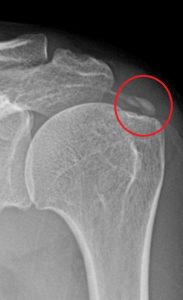

어깨 석회화 건염

어깨 석회화 건염 안녕하세요 고래한의원 박대명 원장입니다. 오늘은 ‘어깨 석회화 건염’에 대해 말씀드리겠습니다. ‘어깨 석회화 건염’은 어깨 힘줄 부위에 석회 성분이 쌓이면서 통증을 유발하고, 관절의 움직임 범위에도 영향을 주는 상태입니다....